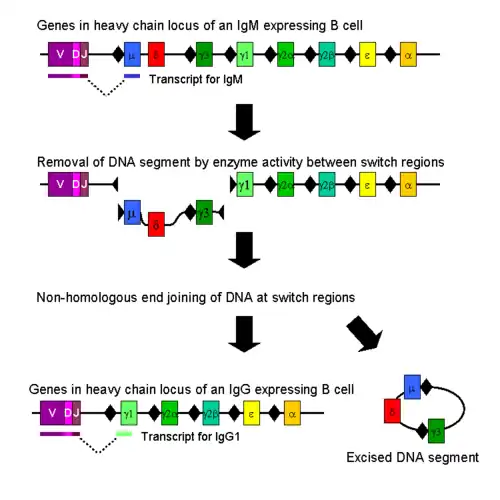

IgM is the form of antibody that all B cells produce initially before they undergo class switching due to exposure to a recognized antigen. Healthy B cells efficiently switch to other types of antibodies as needed to attack invading bacteria, viruses, and other pathogens. In people with hyper IgM syndromes, the B cells keep making IgM antibodies because they can't switch to a different antibody. This results in an overproduction of IgM antibodies and an underproduction of IgA, IgG, and IgE.[11][7]

CD40 is a co-stimulatory receptor on B cells that, when bound to CD40 ligand (CD40L), sends a signal to the B-cell receptor.[12] When there is a defect in CD40, this leads to defective T-cell interaction with B cells. Consequently, humoral immune response is affected. Certain insults, usually from encapsulated bacteria and toxin, then have a greater opportunity to damage the body.[1]

- Hyper-IgM syndrome type 1 (X-linked), characterized by mutations of the CD40LG gene. In this type, T cells cannot tell B cells to switch classes.[2]

- Hyper-IgM syndrome type 2 (autosomal recessive), characterized by mutations of the AICDA gene. In this type, B cells cannot recombine genetic material to change heavy chain production[3]

- Hyper-IgM syndrome type 3 characterized by mutations of the CD40 gene. In this type, B cells cannot receive the signal from T cells to switch classes.[4]

- Hyper-IgM syndrome type 4 which is a defect in class switch recombination downstream of the AICDA gene that does not impair Somatic Hypermutation.[13]

- Hyper-IgM syndrome type 5 characterized by mutations of the UNG gene.[5]